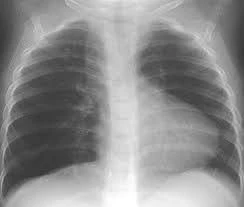

- X Quang: Tim hình hia (boot shaped heart)